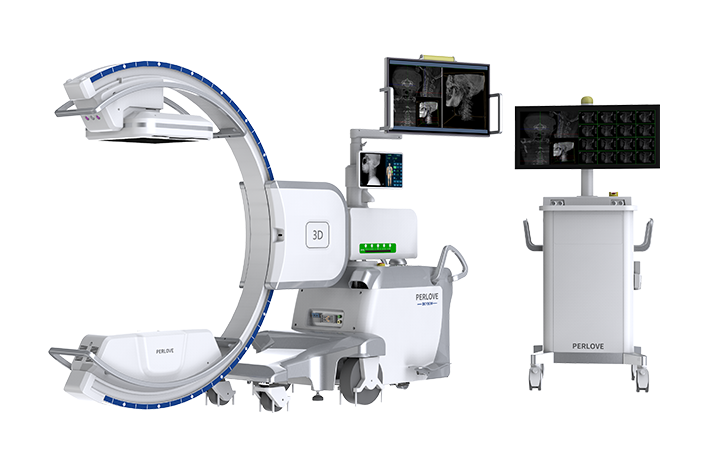

PLX C7500A

移动式C形臂X射线机

开创三维影像“新视界” PLX C7500A

成像清晰、操作简易、摆位便捷,主要适用于骨科、脊柱外科、矫形外科、创伤骨科及手术室等,能大幅度提升手术水准,降低手术风险和并发症的概率。